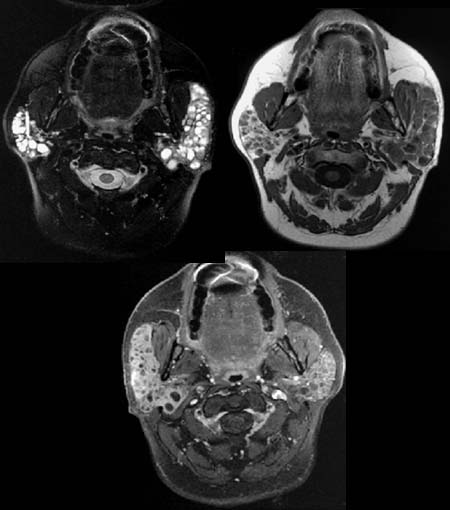

Die

Glandula parotis kommt in T2-Wichtung wabenartig

signalangehoben zur Darstellung. Die zystischen Areale kommen zum Teil

signalreich

oder signalärmer

zur Darstellung.

In T2-Wichtung nativ kommt die Glandula parotis beidseits

weitgehend signalarm zur Darstellung.

Nach Kontrastmittelgabe nimmt das Parenchym Kontrastmittel auf, die

zystischen Anteile bleiben signalarm.